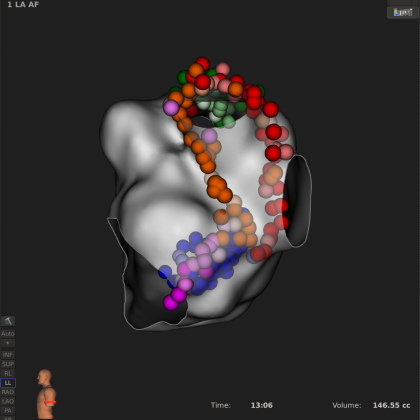

近日,中山大学附属第一医院在何建桂主任指导下,成功完成了首台基于DIRECTSENSE™局部阻抗技术的持续性房颤射频消融手术。作为房颤射频消融手术的新型诊疗工具,该技术通过配合RHYTHMIA HDx™心脏电生理三维标测系统和INTELLANAV™ MiFi OI磁定位微电极盐水灌注消融导管,可在手术过程中监测局部阻抗变化,助力医者对消融状况进行实时评估,从而优化诊疗手术方案,满足患者多样化的疾病诊疗需求。

手术过程:

ABL strategy:CPVI+顶部线+后壁底部线+MVI

DS数据回顾汇总(SL1长鞘辅助下):

此外,何建桂教授本次房颤手术使用了DIRECTSENSE™软件中的Auto Tag(自动取点)功能,设置参数如下:Max Distance:5mm;Min Time:3s;DS impedance Drop:5Ω-13Ω。